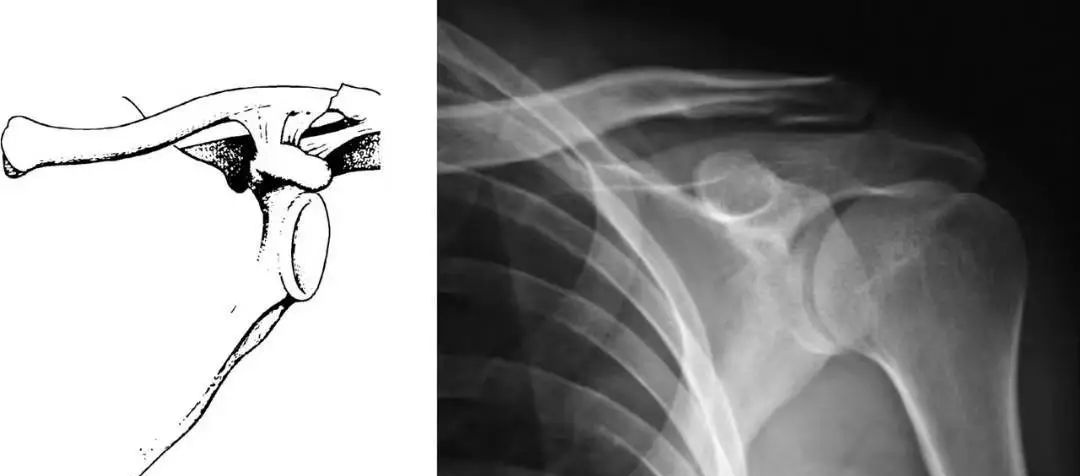

对于CraigⅡ、Ⅴ型不稳定锁骨远端骨折来说,造成不稳定的力量来自以下四个方面:上肢的重力,胸大肌、胸小肌和背阔肌的牵拉,肩胛骨的旋转,斜方肌对骨折内侧端向后上方的牵拉。以上因素使得不稳定的锁骨远端骨折非手术治疗的不愈合率可达到22%~33%。

手术治疗方法包括1~枚克氏针、螺纹针、螺丝钉经肩峰进行固定、喙锁螺丝钉固定、喙突移位、张力带以及接骨板等。目前多采用锁骨钩接骨板进行复位后的固定,该治疗方法具有固定物放置容易、可较为准确的维持复位、不破坏肩锁关节、内固定物相对稳定等优点,不会像传统的克氏针一样向周围组织发生滑移。但该治疗方式易导致患者在术后功能锻炼时产生的应力沿肩锁关节向锁骨传导,在接骨板的内侧部位造成应力集中,并出现应力骨折。